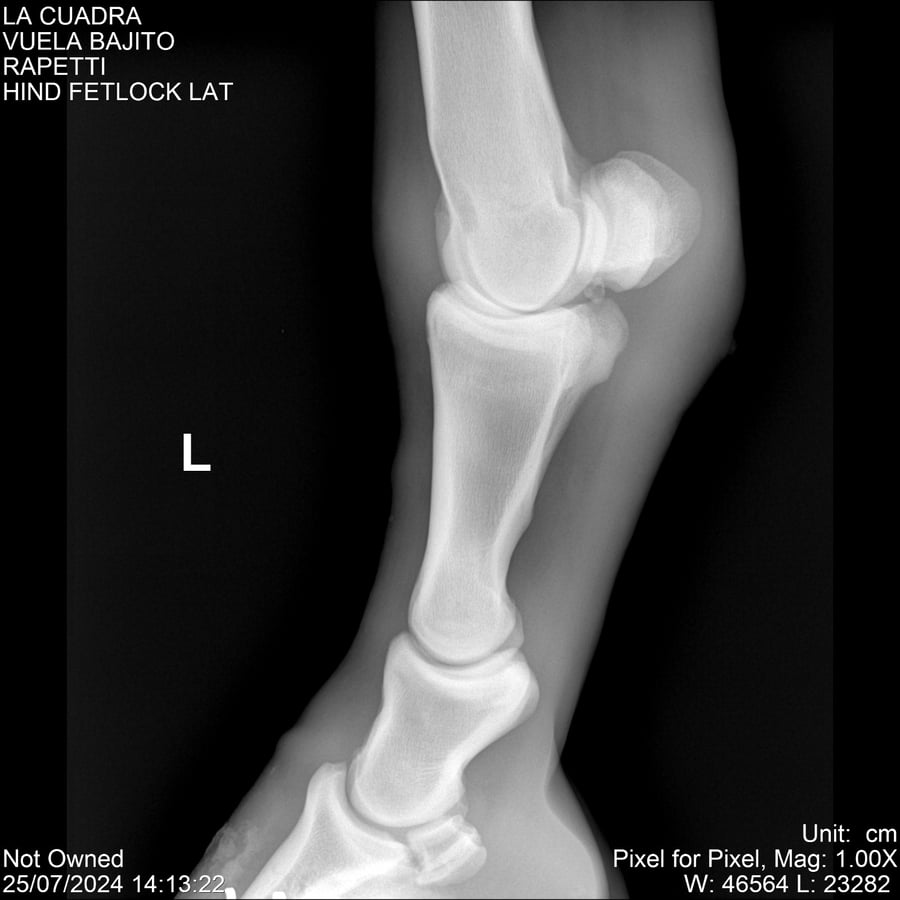

LOTE 16, VUELA BAJITO Lote Anterior Volver al remate Lote Siguiente Ficha Contacto Montevideo - Ficha del Lote Identificador: #284451 Categoría: Yeguarizos Montevideo - 77 Visualizaciones ClicData Contacto Empresa: Abelenda N. R., Walter Hugo Nombre*: Teléfono* : E-mail* : Mensaje Enviar Registrese gratis Este contenido Exclusivo está disponible sólo para usuarios registrados Ingresar